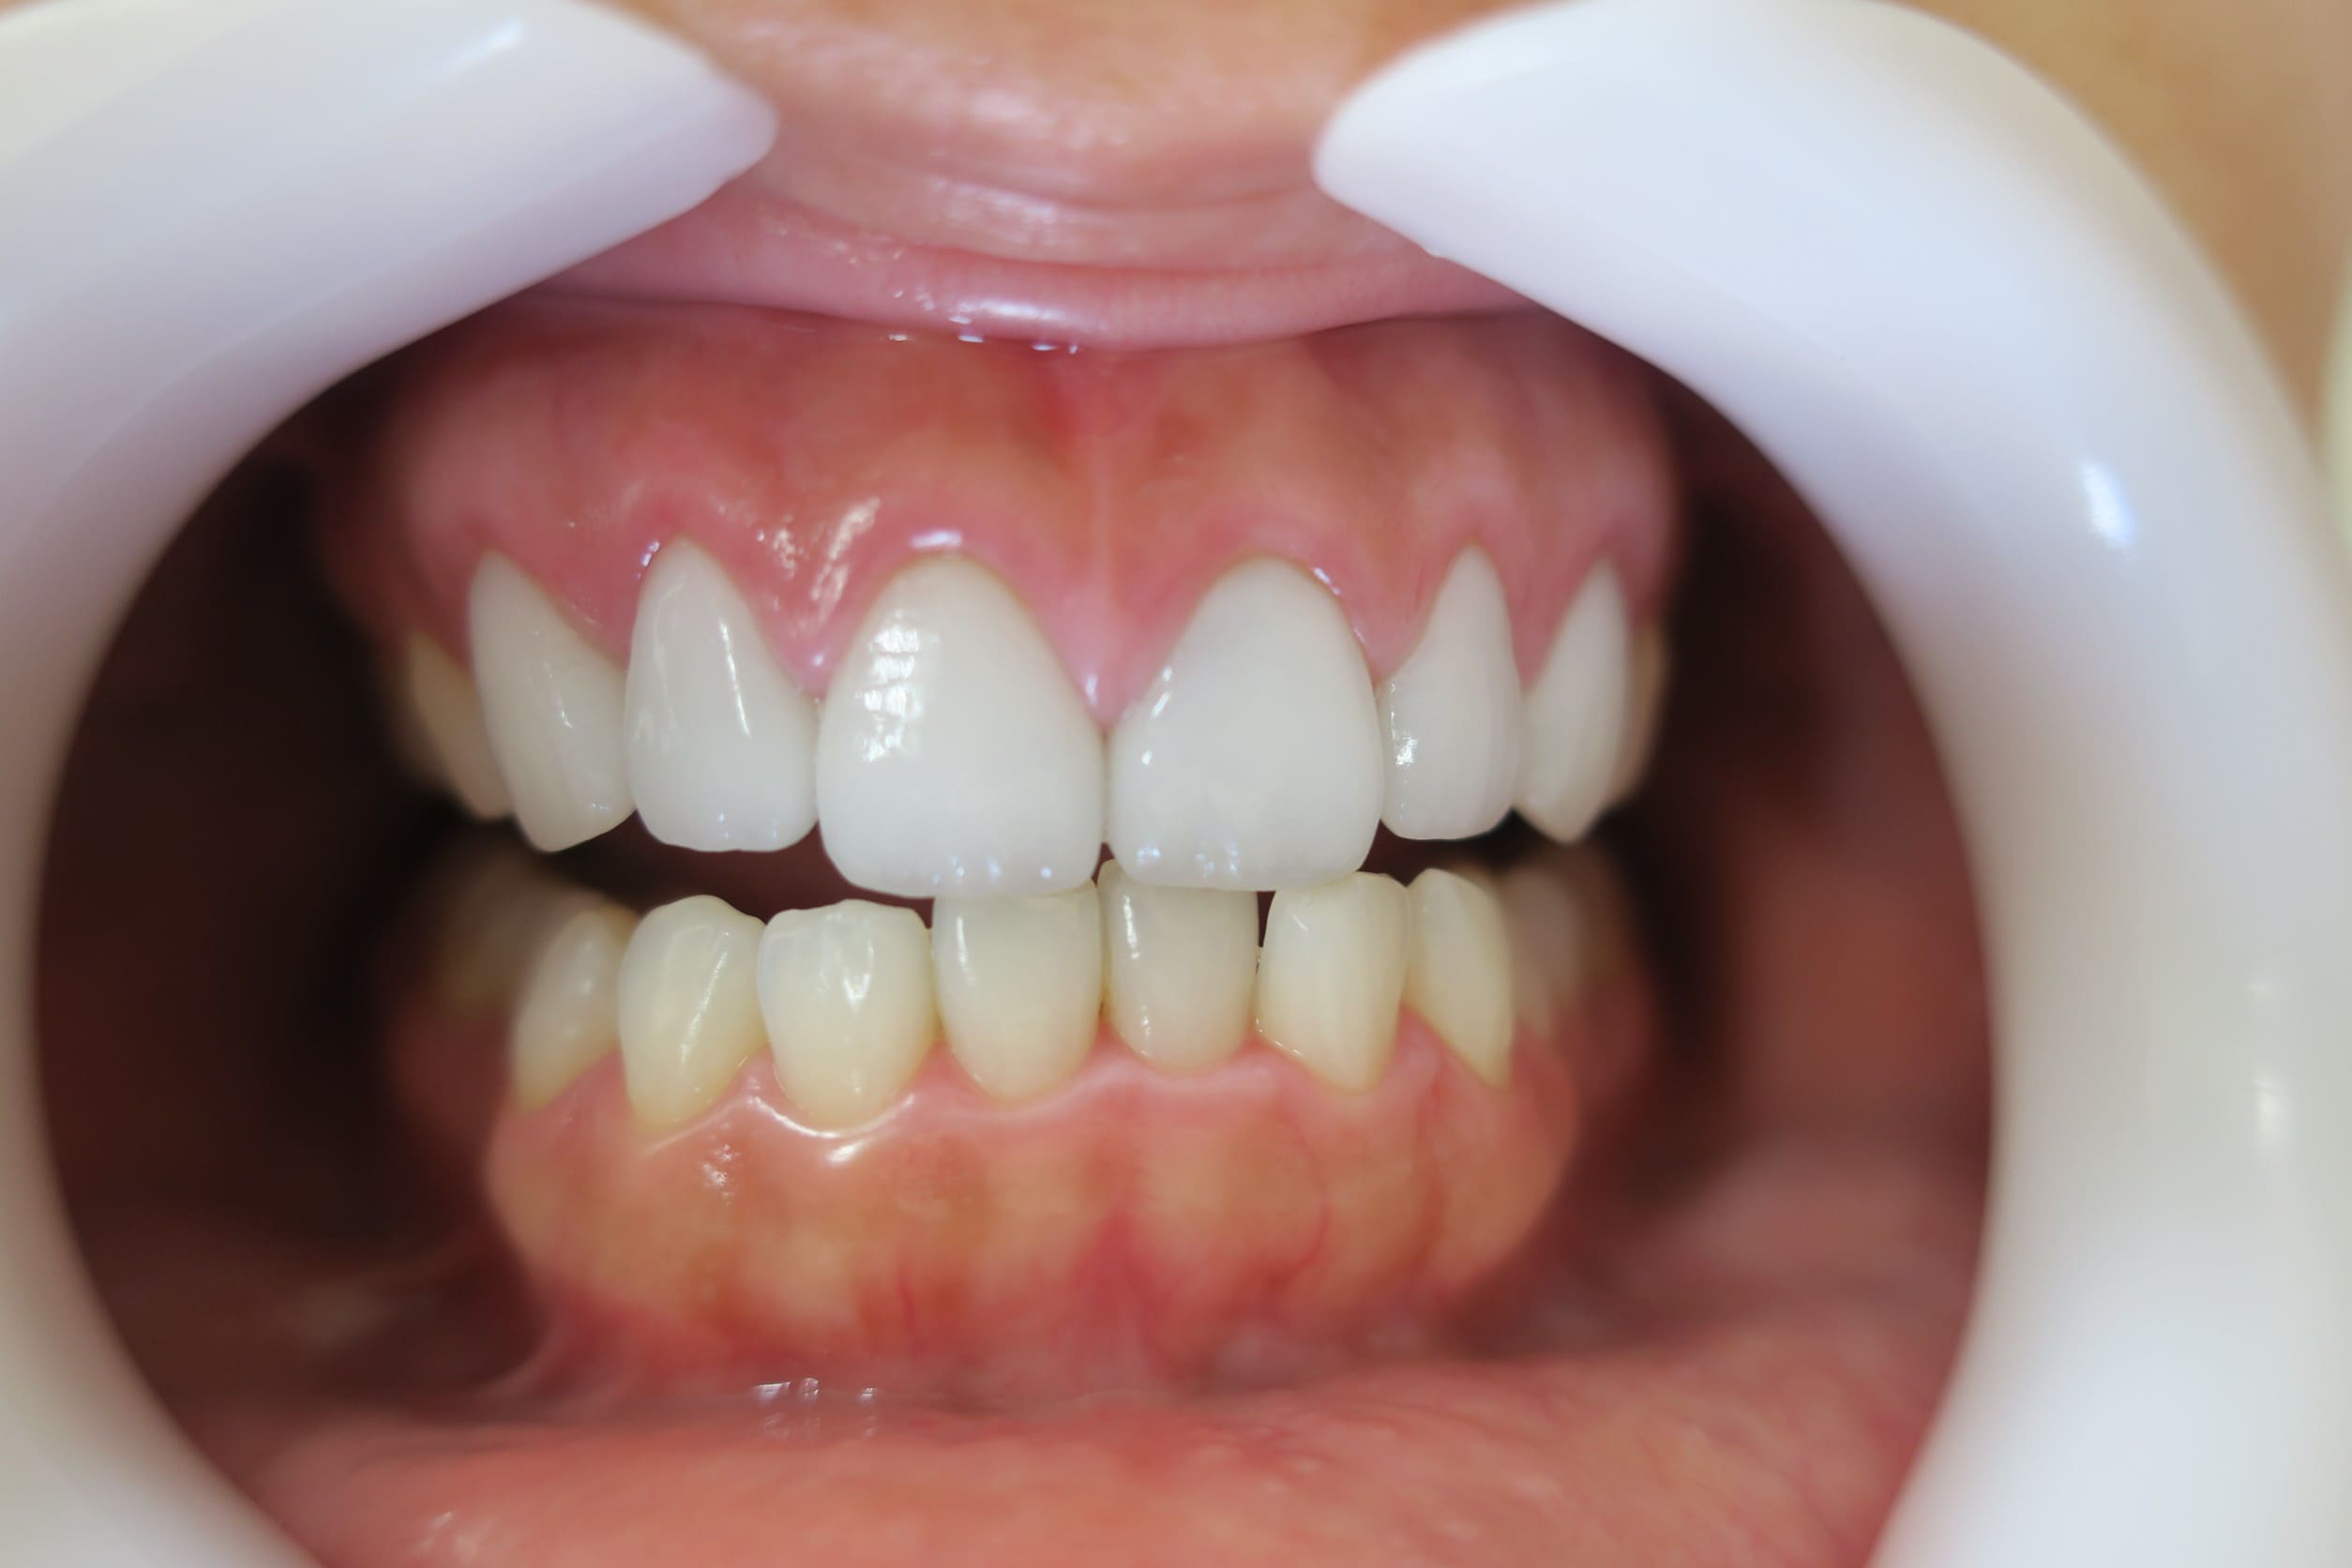

クリアブラケットを選択された患者様はホワイトワイヤーと透明ゴムを使用することで、見た目が目立ちにくくなります。また、各色カラーゴムもご用意しており、追加料金はかからずに選んでいただけます。

藤沢デンタルオフィスのワイヤー矯正 藤沢デンタルオフィスのワイヤー矯正